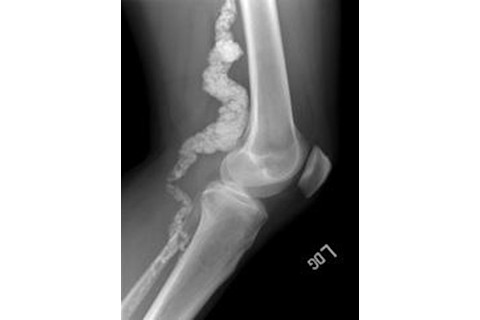

2009年,该项目收到了一位肯塔基州医生的转介,涉及两位患有关节疼痛的姐妹,Paula Allen和Louise Benge,她们的X光片显示动脉有钙沉积……“这些图像让我们震惊,”[项目主任William] Gahl说。研究团队获得了这对姐妹和其他家庭成员(Allen和Benge的三个兄弟姐妹患有同样的隐性疾病)的DNA样本,并扫描DNA寻找称为单核苷酸多态性的标记,研究人员利用这些标记来缩小疾病基因的位置。通过研究另外两个患有类似疾病的家庭的这个基因区域,研究人员能够确定一个特定基因NT5E的突变,该基因参与动脉钙化的分解。[ScienceInsider]

这种新的遗传病被命名为ACDC(抱歉,音乐迷们),代表“CD73缺乏引起的动脉钙化”。研究人员认为这次调查和诊断是该项目的一项重大成就。